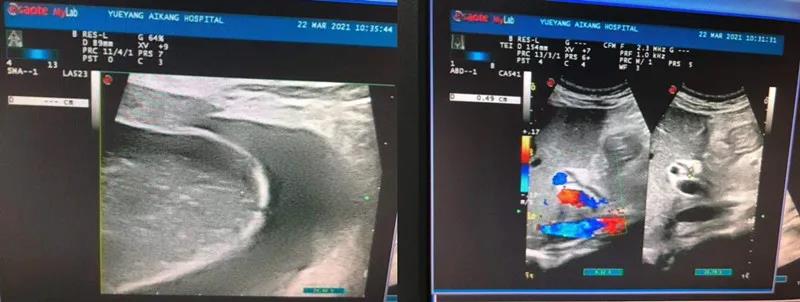

彩超檢查結(jié)果顯示:膽囊腫大、膽囊結(jié)石、急性膽囊炎

劉主任得知檢查結(jié)果后,迅速請普外科醫(yī)生會診。普外科周旭陽主任看到彩超結(jié)果單,提出需盡快手術(shù),否則隨時有穿孔的危險。而劉主任則擔(dān)心手術(shù)會發(fā)生產(chǎn)褥期感染,影響產(chǎn)后恢復(fù)。然而周主任的診療方案很快消除了劉主任的擔(dān)憂,張女士被迅速轉(zhuǎn)入普外科。